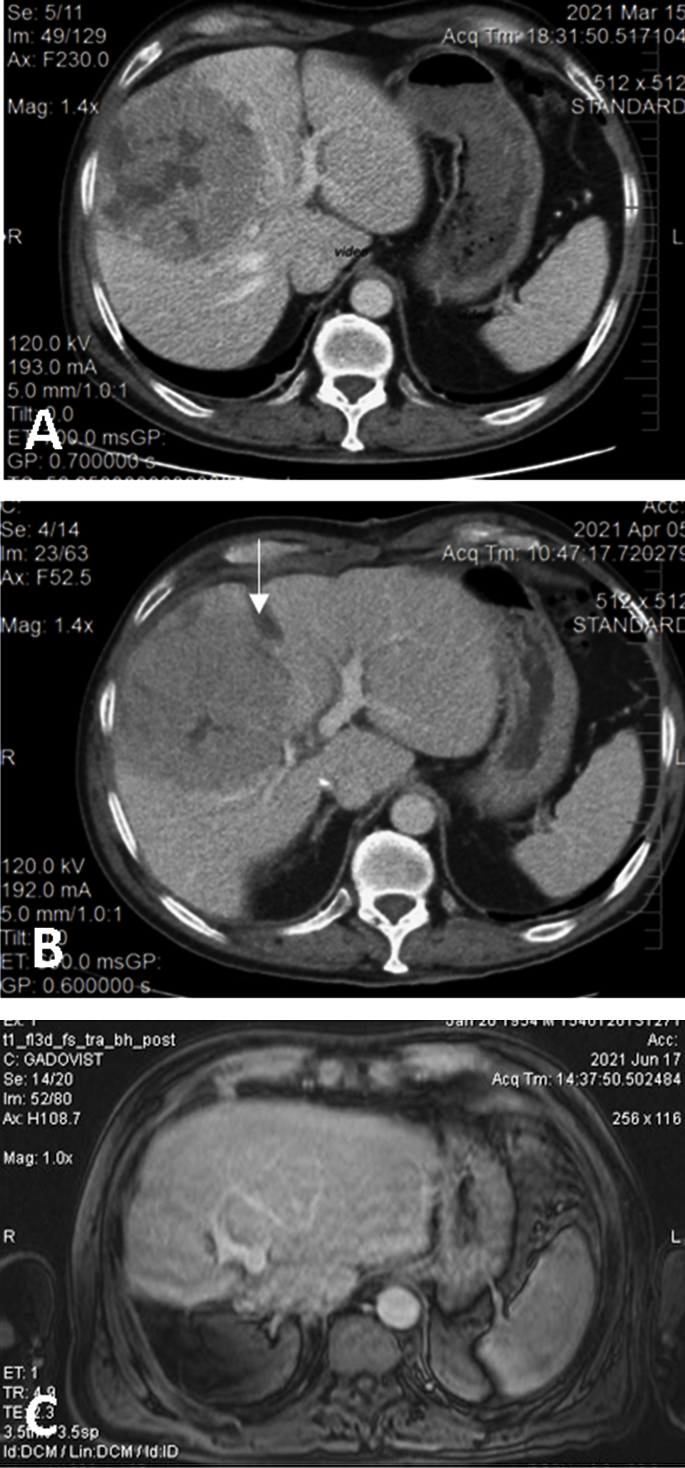

Figure 2. (A). Preoperative CT showing the large HCC located in segments 5 and 8 with extension to segments 6, 7, 4, compressing the middle hepatic vein; volumetry: volume of segments 2 and 3, 16.8% of total functional liver volume, volume of FLR 27.8%. (B) Interstage CT showing the liver partitioning, absence of contrast in the right portal vein (due to ligation), and sufficient growth of FLR (38.5% of total functional liver volume). (C) Postoperative CT with well-perfused, non-dilated bile ducts, and tumor-free remnant liver.